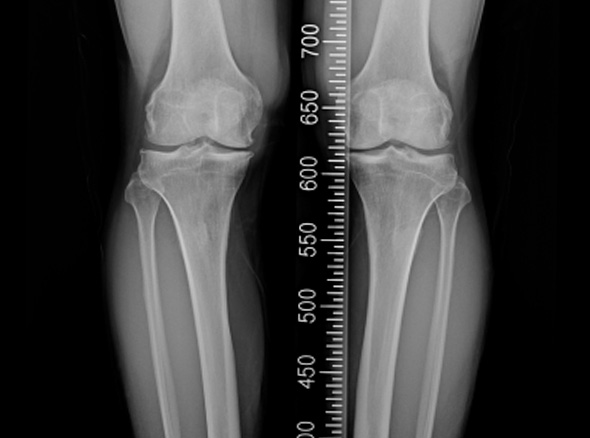

한국인의 대부분에게서 무릎 내측에 무릎 관절염이 발생됩니다.

관절염의 수술적 치료로는 인공관절 수술이 가장 흔하지만, 인공관절 수술을 할 만큼

연골 손상이 심하지 않다면 내측으로 치우친 체중 부하를 정상적인 외측 관절로

이동시키는 ‘무릎관절 교정 절골술’을 시행합니다.